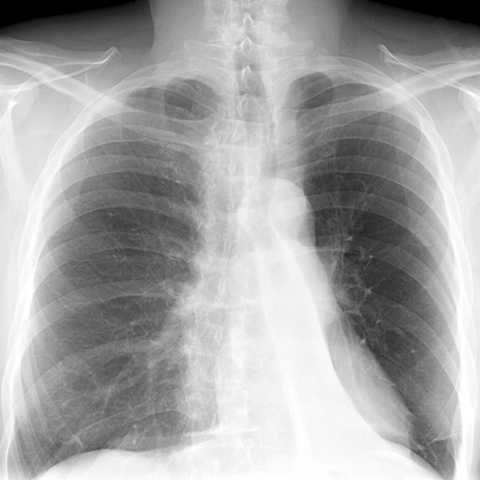

LLL Atelectasis [1 of 4]